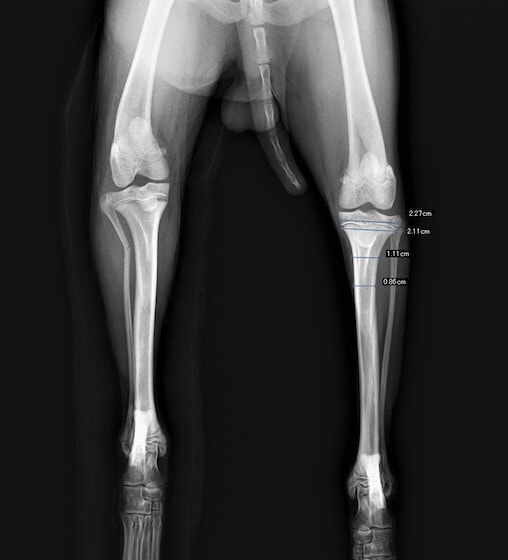

症例3:キルシュナーワイヤーのピンニングによる整復

ペルシャ猫 11ヶ月齢 雄

他院にて左大腿骨遠位の成長板骨折(salter-harrisⅠ型)が認められており、治療相談を目的として来院。当院にて、キルシュナーワイヤーを用いたピンニングにより骨折部位の整復を行いました。術後の経過は良好で、現在も経過観察中です。

術前レントゲン

術後レントゲン